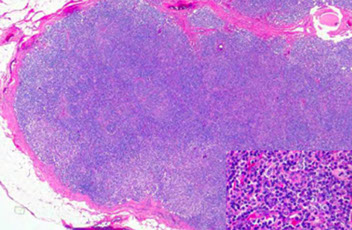

Kikuchi-Fujimoto disease [3] - Classic low-power appearance with reactive follicles at the periphery and paracortical expansion.

Kikuchi-Fujimoto disease [3]